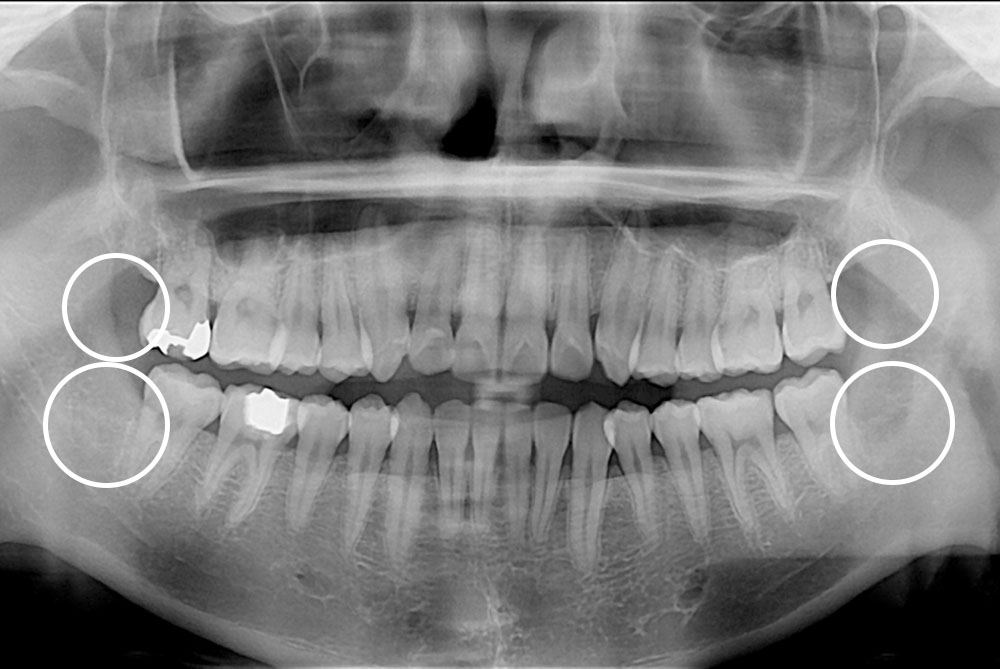

[사랑니] 매복 사랑니 발치

치료후 : 2019-08-22